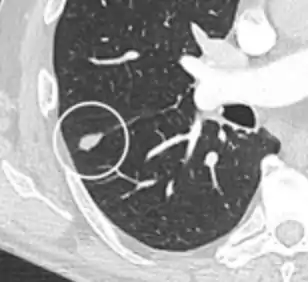

A "notch sign".[9]

A triangular perifissural node can be diagnosed as a benign lymph node.[9]